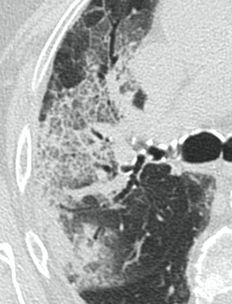

4.3. ЛУЧЕВАЯ ДИАГНОСТИКА COVID-19

Методы лучевой диагностики применяют для выявления COVID-19 пневмоний, их осложнений, дифференциальной диагностики с другими заболеваниями легких, а также для определения степени выраженности и динамики изменений, оценки эффективности проводимой терапии.

К методам лучевой диагностики патологии ОГК пациентов с предполагаемой/установленной COVID-19 пневмонией относят:

- Обзорную рентгенографию легких (РГ),

- Компьютерную томографию легких (КТ),

- Ультразвуковое исследование легких и плевральных полостей (УЗИ).

Стандартная РГ имеет низкую чувствительность в выявлении начальных изменений в первые дни заболевания и не может применяться для ранней диагностики. Информативность РГ повышается с увеличением длительности течения пневмонии. Рентгенография с использованием передвижных (палатных) аппаратов является основным методом лучевой диагностики патологии ОГК в отделениях реанимации и интенсивной терапии (ОРИТ). Применение передвижного (палатного) аппарата оправдано и для проведения обычных РГ исследований в рентгеновском кабинете. В стационарных условиях относительным преимуществом РГ в сравнении с КТ являются большая пропускная способность. Метод позволяет уверенно выявлять тяжелые формы пневмоний и отек легких различной природы, которые требуют госпитализации, в том числе направления в ОРИТ.

КТ имеет высокую чувствительность в выявлении изменений в легких, характерных для COVID-19. Применение КТ целесообразно для первичной оценки состояния ОГК у пациентов с тяжелыми прогрессирующими формами заболевания, а также для дифференциальной диагностики выявленных изменений и оценки динамики процесса. КТ позволяет выявить характерные изменения в легких у пациентов с COVID-19 еще до появления положительных лабораторных тестов на инфекцию с помощью МАНК. В то же время, КТ выявляет изменения легких у значительного числа пациентов с бессимптомной и легкой формами заболевания, которым не требуется госпитализация. Результаты КТ в этих случаях не влияют на тактику лечения и прогноз заболевания при наличии лабораторного подтверждения COVID-19. Поэтому массовое применение КТ для скрининга асимптомных и легких форм болезни не рекомендуется.